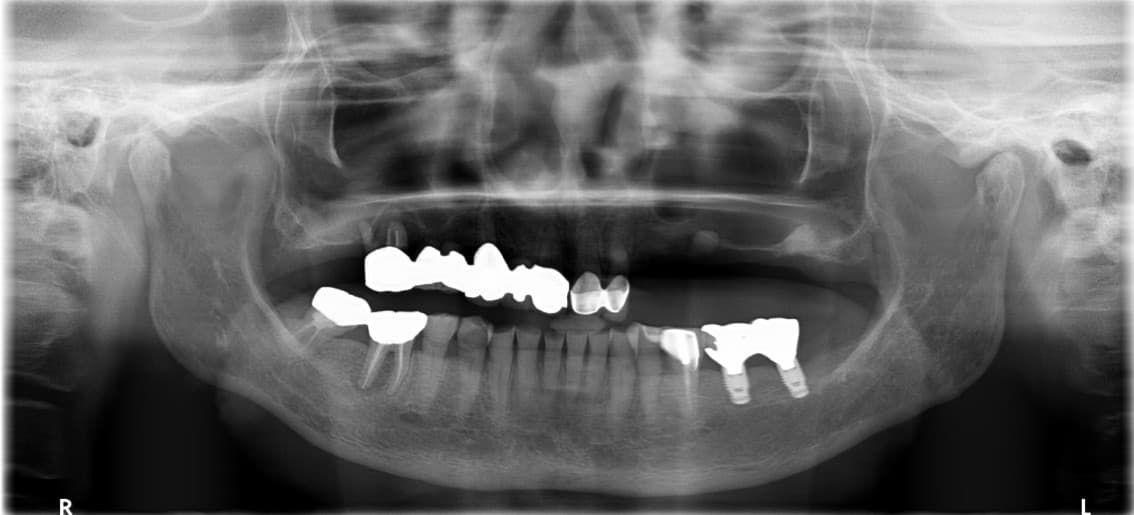

Park●● · 70 yoshdan oshgan erkak

Pastki jag to'liq implant